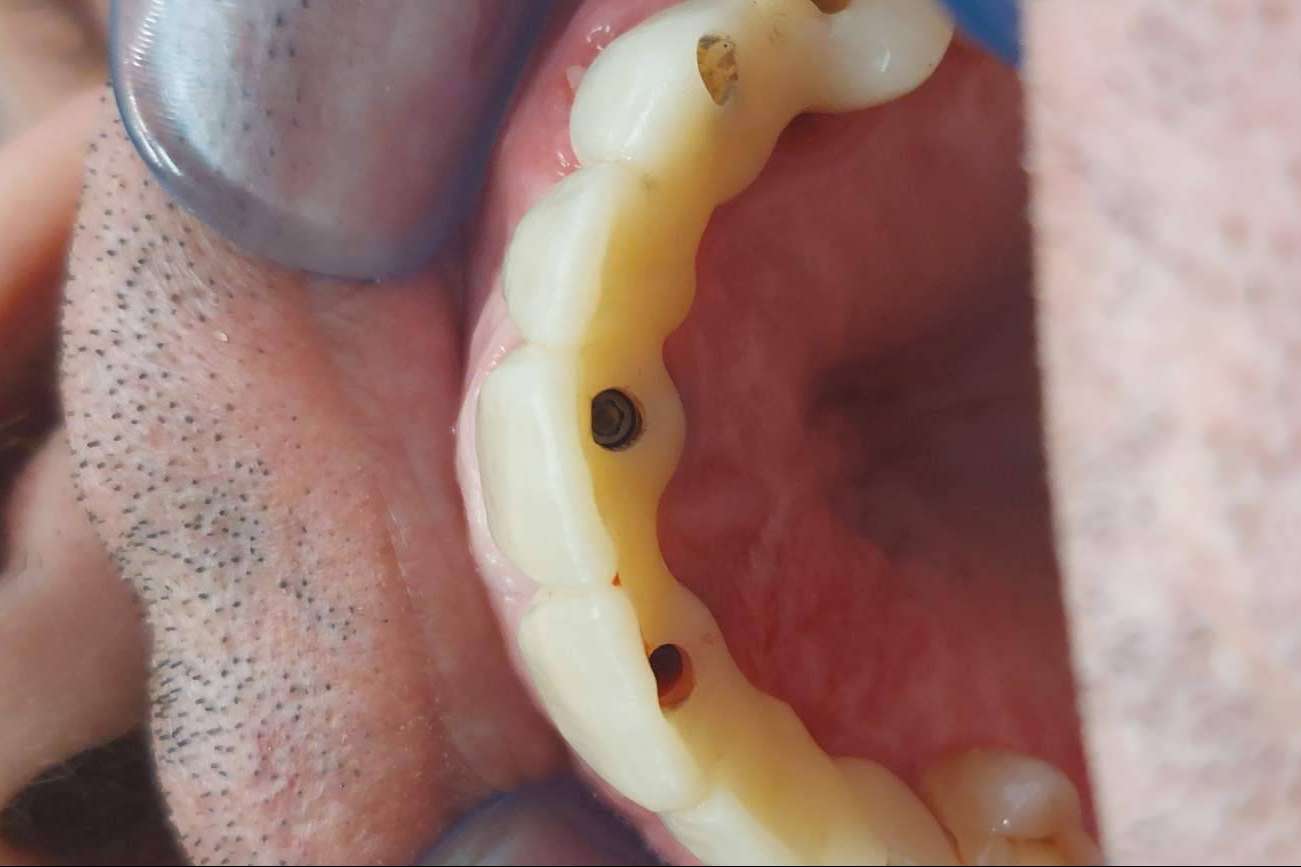

Una vez realizadas las incisiones en el maxilar, se limpia la boca por completo. El paso siguiente es el de la colocación de la prótesis, que se fabrica mediante procesos robotizados y el uso de materiales de gran calidad. Ese mismo día se produce la fijación total de los implantes y el paciente recupera todas las funciones que había perdido. Su calidad de vida mejora instantáneamente y, en poco tiempo, se acostumbra a su nueva dentadura.

Las prótesis, que mediante la tecnología son diseñadas a medida, resultan sumamente higiénicas y estéticas. El paciente recupera la sonrisa, rejuvenece su aspecto y mejora notablemente la forma en que luce su rostro. A la vez, las molestias que se generan son mínimas y las visitas necesarias a los odontólogos e implantólogos son menores que con otros tipos de tratamientos. En Dentinova, es posible acceder a la colocación de implantes dentales All-On-4 y recuperar la dentadura en un solo día.